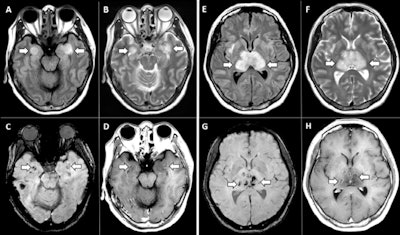

CT and MRI imaging showed the following:

- Head CT images showed symmetric hypoattenuation within the bilateral medial thalami with a normal CT angiogram and CT venogram.

- Brain MRI images showed T2-weighted and fluid-attenuated inversion recovery (FLAIR) hyperintensity within the bilateral thalami, medial temporal lobes, and subinsular regions with areas of hemorrhage, as well as rim enhancement on postcontrast images.

"Accumulating evidence suggests that a subgroup of patients with severe COVID-19 might have a cytokine storm syndrome," the team wrote. "The most characteristic imaging feature includes symmetric, multifocal lesions with invariable thalamic involvement. Other commonly involved locations include the brain stem, cerebral white matter, and cerebellum."